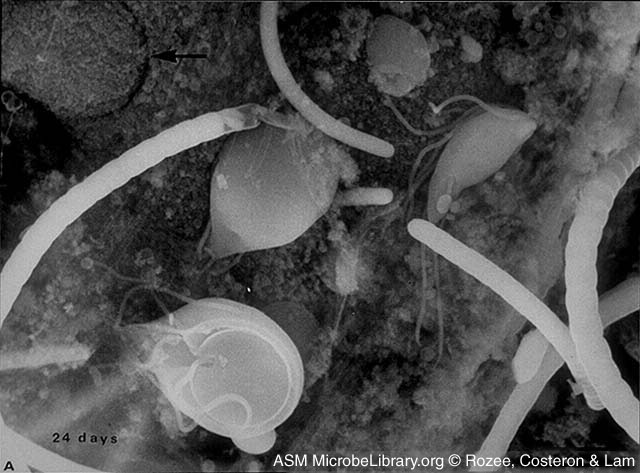

Scanning Electron Micrograph of Giardia and several Bacteria

Adhering to the Wall of the Small Intestine of a Mouse

© Ken Rozee, author. Licensed for use, ASM MicrobeLibrary.